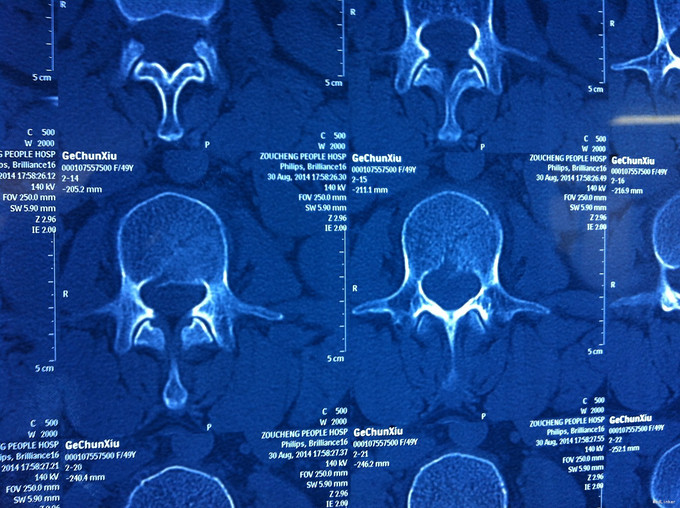

专科查体无下肢神经损伤表现:腰部叩痛,腰部活动受限,双下肢感觉无异常,双下肢肌力4-5级,双侧膝腱反射++,跟腱反射+,双侧巴氏征阴性, X-ray:腰1椎体骨折,累及前中柱,腰3椎体骨折。CT:腰1、3椎体骨折,累及中柱。MR:腰1、3骨折,新鲜骨折。影像学检查提示腰1椎体骨折较重。